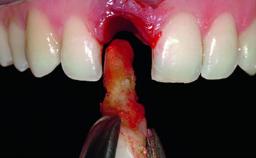

A healthy 28-year-old female patient presented for a consultation on treatment options to restore her upper right central incisor. At the clinical examination, the tooth responded to percussion and palpation. The gingiva was red and slightly swollen, with a mid-facial probing depth of 10 mm. The upper right lateral incisor showed no signs or symptoms, did not respond to exploration and percussion, and the vitality test was positive. The periapical radiograph revealed that tooth 11 had been endodontically treated, with no lesion evident at the apex. A small radiopaque calcified structure surrounded by a narrow radiolucent zone (3 × 3 mm) was present at the apex of tooth 12.

Bone Augmentation | Horizontal|Simultaneous |

Augmentation Materials | Autogenous chips|Xenogenous|Membrane |